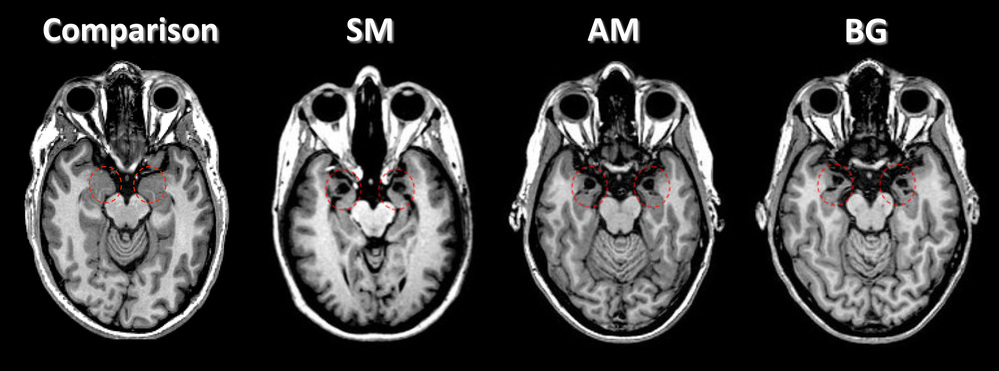

In these brain scans, amygdala damage can be seen in three patients (known as SM, AM and BG) with Urbach-Wiethe disease. See the dark spots within the areas circled in red. A healthy person is shown (left) for comparison.

Corey Feinstein/Iowa Neurological Patient Registry, University of Iowa, Courtesy of Nature In these brain scans, amygdala damage can be seen in three patients (known as SM, AM and BG) with Urbach-Wiethe disease. See the dark spots within the areas circled in red. A healthy person is shown (left) for comparison. In these brain scans, amygdala damage can be seen in three patients (known as SM, AM and BG) with Urbach-Wiethe disease. See the dark spots within the areas circled in red. A healthy person is shown (left) for comparison.